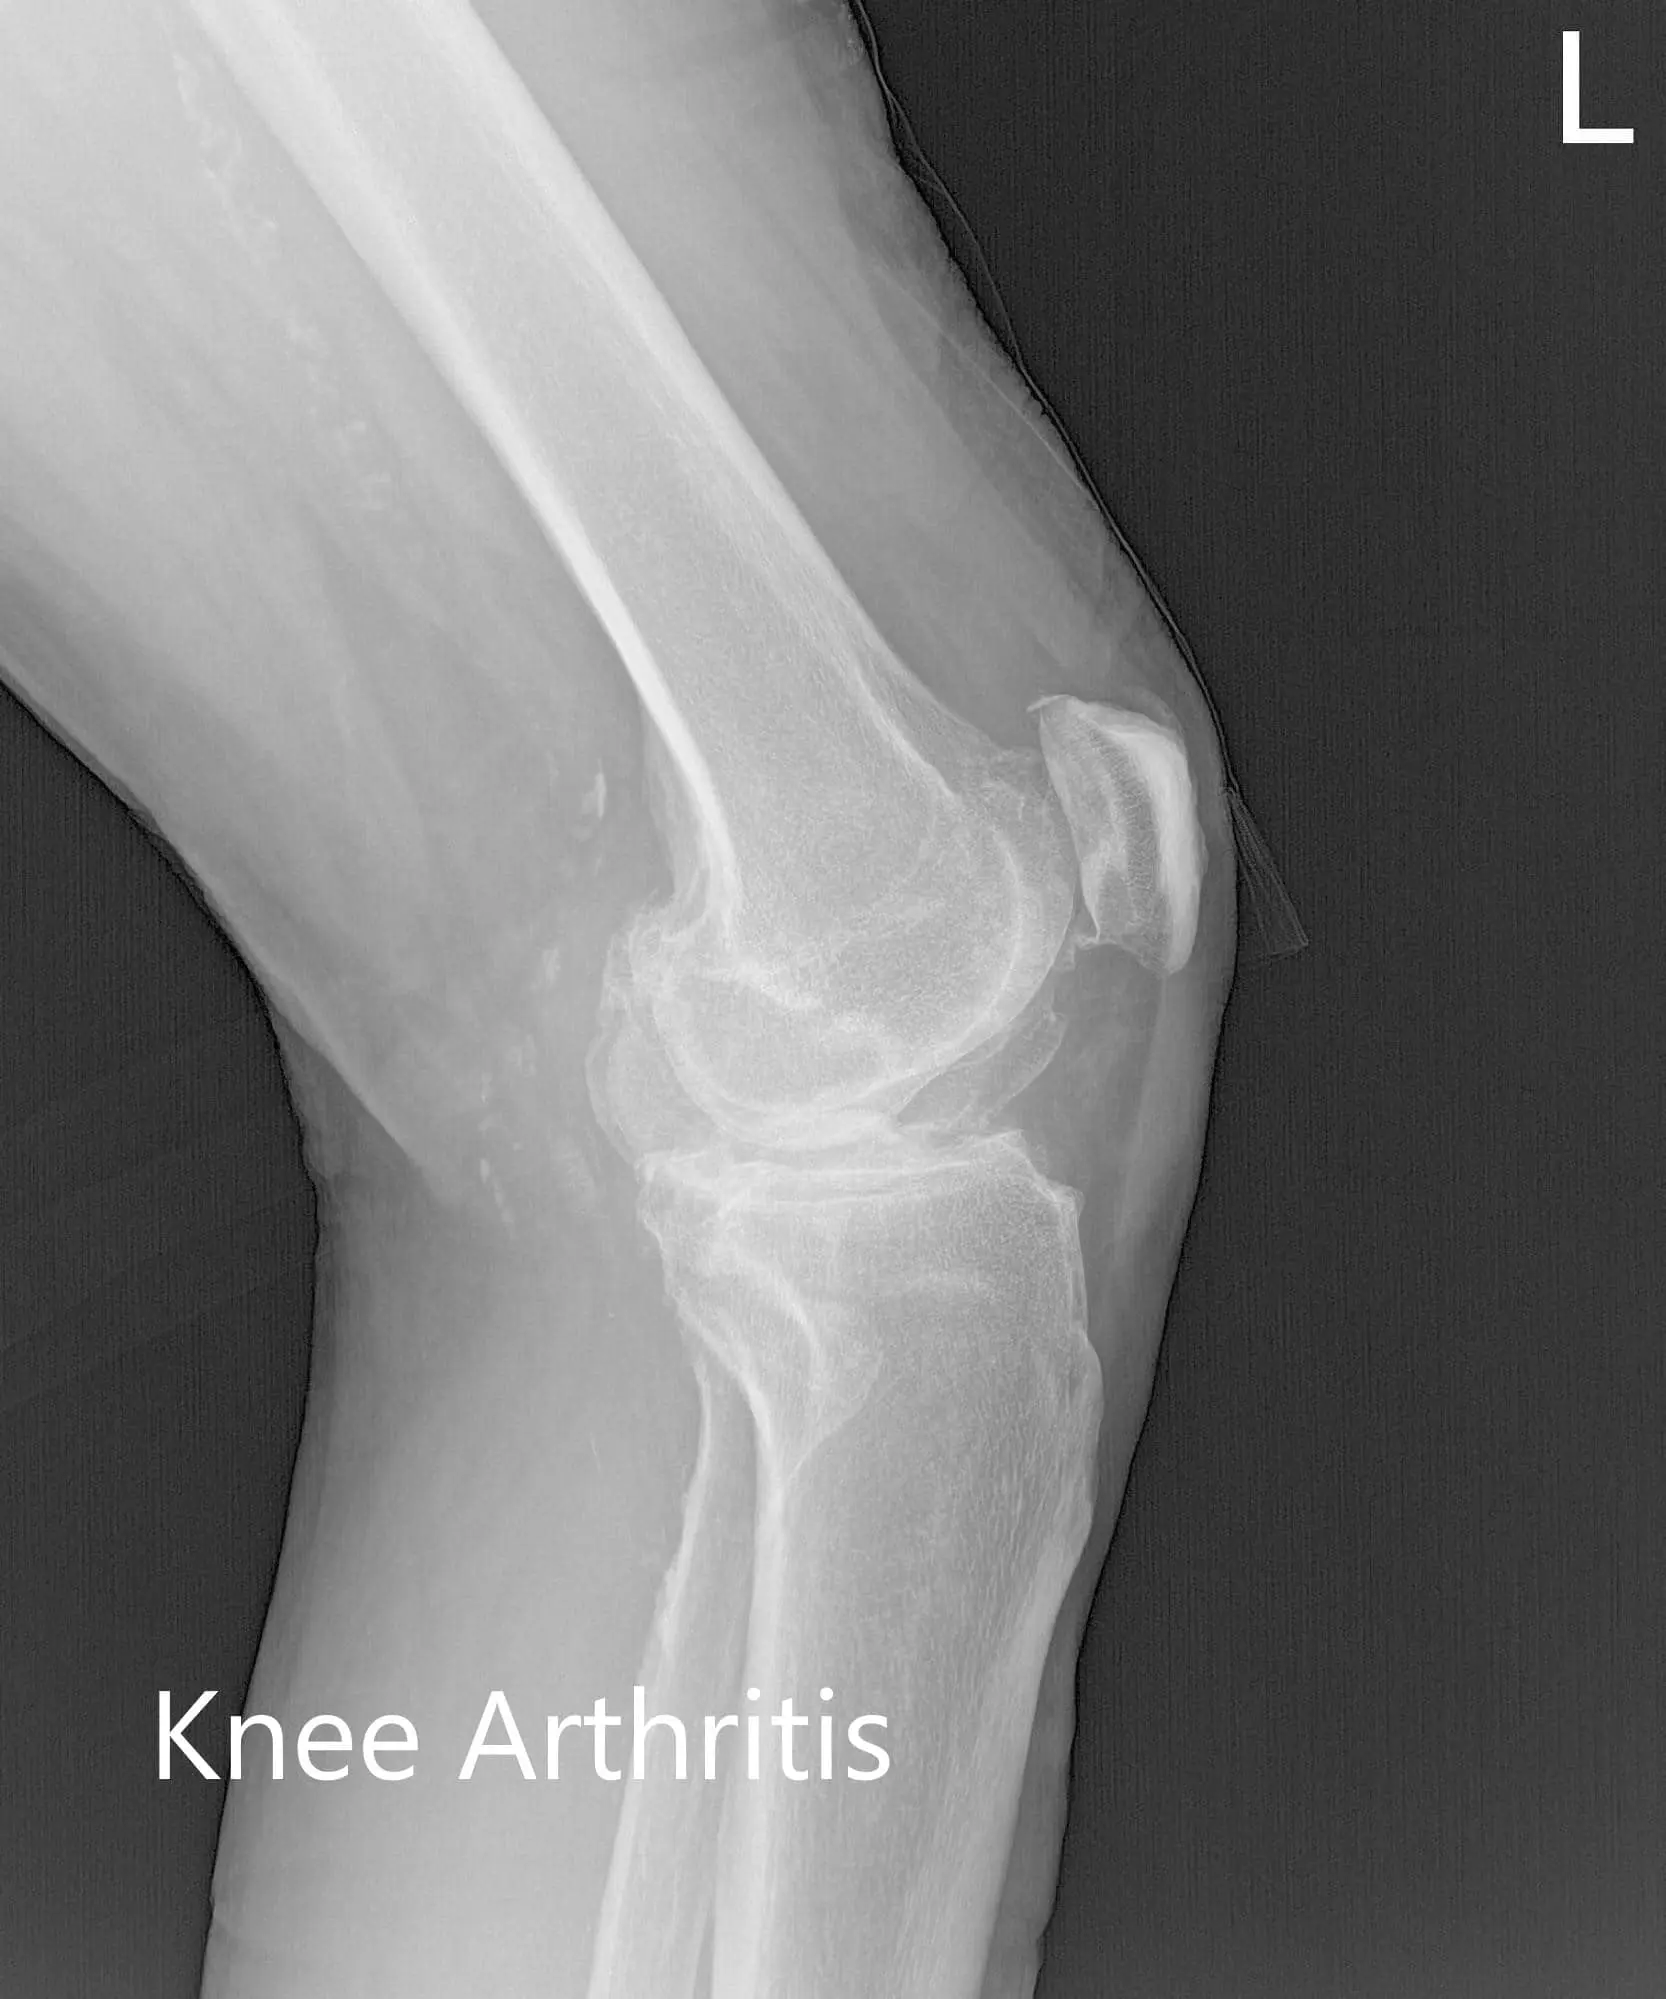

Preoperative X-ray of the left knee showing AP, lateral and merchant views

Preoperative X-ray of the left knee showing AP, lateral and merchant views - img 2

Preoperative X-ray of the left knee showing AP, lateral and merchant views - img 3

There was no distal neurological deficit and the bilateral pulses were good volume and comparable. Imaging studies revealed severe tricompartmental osteoarthritis of the left knee. Considering the patient’s lifestyle limiting knee pain, she was advised customized left knee total replacement. Risks, benefits, and alternatives were discussed with her at length. She agreed with the plan.